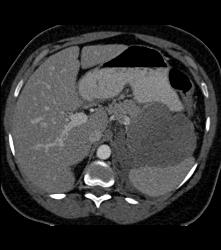

Thickened Gastric Folds